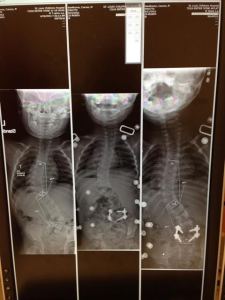

In January of 2013 Michael’s curve increased to 63* and 53” and it was decided it was time to consider surgery. He repeated MRI’s to make sure there were no changes to his spinal cord. He was scheduled for surgery in April but due to some issues with lab work at the very last minute it was continued to May of 2013. His surgeon did a great job of explaining the surgery in detail. It was very hard to hear that the plan was not to “straighten” his spine, but to stop the progression from going any further. He explained that attempting to straighten his spine completely could compromise his spinal cord and was too risky. The thought of going through such a big surgery without the benefit of looking better afterwards was pretty devastating for Michael to hear. The surgeon decided to not fuse the bottom compensating curve to leave him with more flexibility and the hope that it would compensate back. Michael had a pic line put in the day before surgery as an outpatient procedure.

Michael had his first post x-ray at about 6 weeks after surgery. It was amazing to see the difference. He actually gained 2 inches in height when he came home from surgery. This x-ray was the first time we could see his 2 rods and 20 screws. Even though the plan wasn’t to straighten his spine, his back looked great. The compensating curve did not compensate back as hoped so he has a 38* curve on his hip that has stayed consistent.